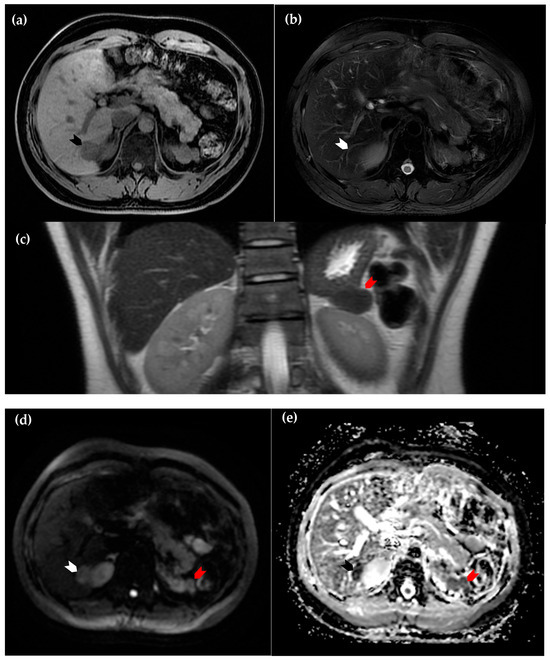

Figure 2. Magnetic resonance imaging of the liver. (a) Axial view of the T1 sequence, in which the intrahepatic lesion is hypointense in comparison to surrounding normal hepatic parenchyma (black arrowhead); (b) axial view of the T2 sequence, in which the lesion is nearly isointense (white arrowhead); (c) coronal view of the T2 sequence. The suspected perinephric splenosis (red arrowhead) again exhibits similar attenuation to the intrahepatic lesion (white arrowhead in (d) and black arrowhead in (e)), as well as characteristics of restricted diffusion on diffusion-weighted imaging (d) and the corresponding apparent diffusion coefficient map (e). These findings support the diagnosis of intrahepatic splenosis [2].